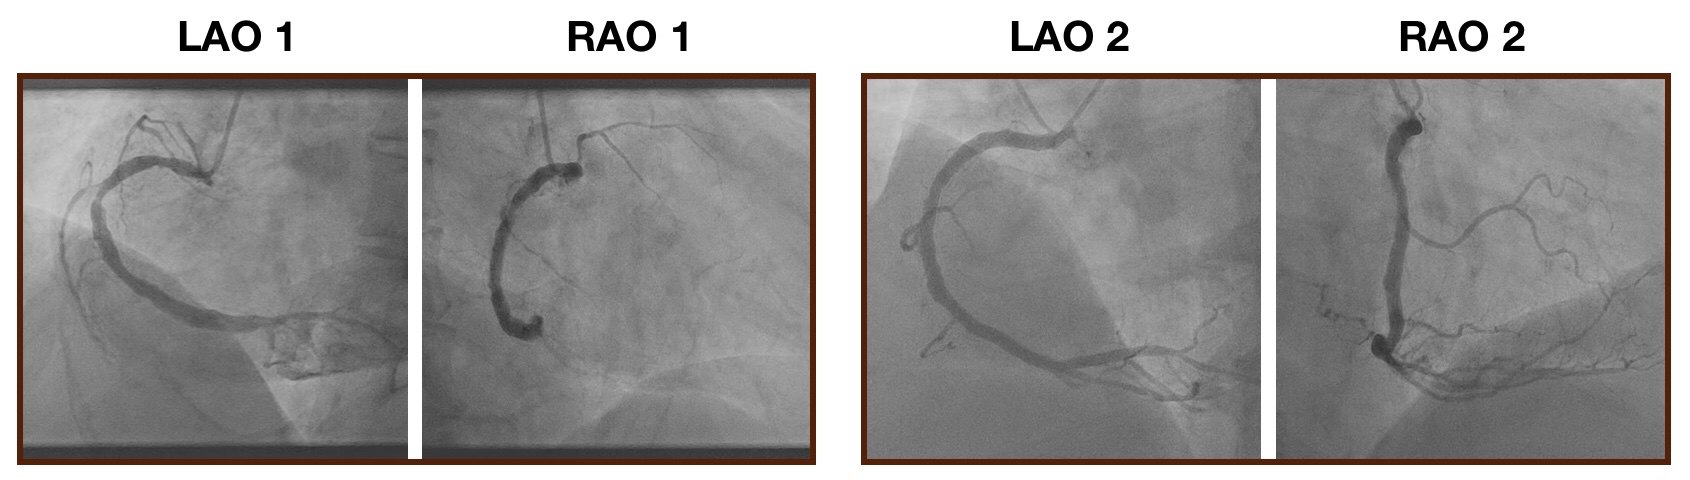

Figure 3: Illustration of LAO and RAO results. (A) Temporal score variation over the course of an LAO angiography video. Each data point represents the machine predicted score of that frame. Three particular frames are highlighted in red as they represent the frame just before, in and after the “key frame region”. (B) Machine’s inferential ability shown by noisy incorrect LAO labels detected by the model. First image: a key frame erroneously labeled as non-key in manual labeling, and the model gave the frame a high score (0.998) Second image: a non-key frame with vessel shifted out erroneously labeled as a key frame; it was detected and given a low score (0.083) (C) LAO vessel segmentation, (a) original images, (b) segmentation masks. (D) RAO vessel segmentation, (a) original images, (b) segmentation masks. (E) Erroneous LAO segmentation near the RCA bifurcation point. (F) Identification of LAO stenosis location and estimation of severity. (G) Side-by-side comparisons between LAO and RAO stenosis measurement. Each column represents one patient.

where predictionprediction\operatorname{prediction} and truelabeltruelabel\operatorname{truelabel} are arrays representing generated and ground-truth masks respectively. Our segmentation model can localize heart vessels with relatively high precision (Fig. 3C). Comparing the performance of our model with Yang et al. [19], our model using a similar but much smaller training dataset (102 vs 1021 patients) was able to reach a comparable result (Table. III). Our neural network architecture was also of lower complexity, requiring less computational power for training, albeit prone to errors especially near the distal RCA bifurcation (Fig. 3E). More complex U-Net architectures and more training data will improve the performance in these difficult areas.